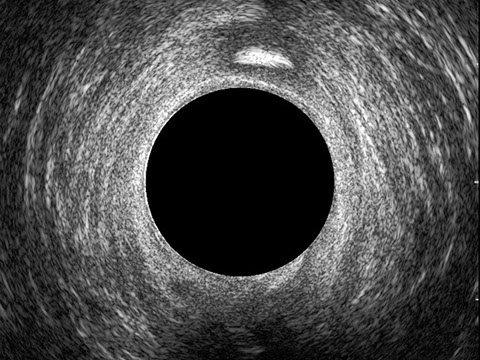

L’ecografia transanale è un esame diagnostico per immagini che consiste nell’introduzione di un trasduttore ad ultrasuoni. Le immagini qualitativamente migliori del canale anale sono ottenute usando un trasduttore rotante, montato in un manipolo rigido, che fornisce un’immagine a 360°. Con le apparecchiature più moderne è anche possibile ottenere immagini tridimensionali.

L’ecografia transanale permette di distinguere la sottomucosa che riveste il canale anale, lo sfintere anale interno, e lo sfintere anale esterno.

Le principali indicazioni all’esecuzione di tale esame sono lo studio dell’integrità delle strutture muscolari nei casi di incontinenza fecale, lo studio topografico dei processi settici perianali (ascessi e fistole) e lo studio dei processi proliferativi epiteliali (carcinoma anale).